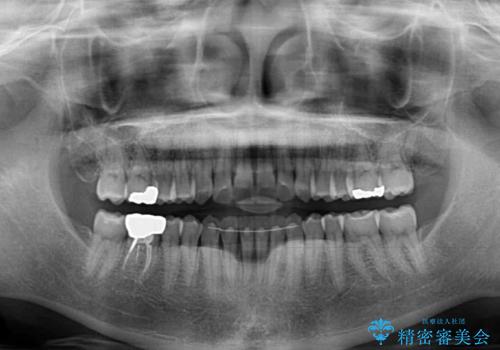

- 前歯のデコボコを治したいとのことで来院された患者様です。

上下顎ともに歯列全体の後方移動とIPR(歯と歯の間を削る)によってデコボコが解消するように設計し、インビザラインにより治療を行うこととしました。